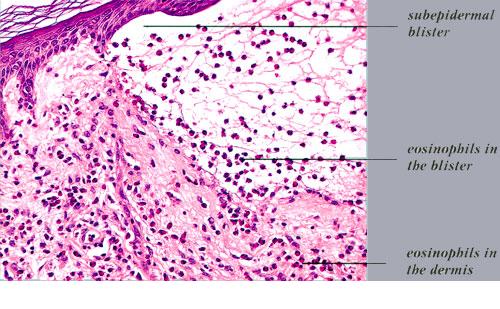

Histopathology.

In early lesions, papillary dermal edema in combination with a cell-poor or cell-rich perivascular lymphocytic and eosinophilic infiltrate is present. The blister arises at the dermal-epidermal junction . In the cell-rich pattern, which correlates clinically with blisters arising on erythematous skin , eosinophilic papillary abscesses may develop with numerous perivascular and interstitial eosinophils intermingled with lymphocytes and neutrophils in the superficial and deep dermis. Early lesions may have the histologic features of eosinophilic cellulitis (Well’s syndrome). Eosinophilic spongiosis may occur. The cell-poor pattem is observed

when blisters develop on relatively normal skin , in which there is usually a scant perivascular lymphocytic infiltrate with few eosinophils, some scattered throughout the dermis and others near the epidermis. The blister contains few inflammatory cells. Epithelial migration and regeneration may result in an intraepidermal split in older blisters. Similar to pemphigus vegetans, a hyperplasia of the epidermis, subepidermal bullae, and accumulations of eosinophils and lymphocytes may be seen.